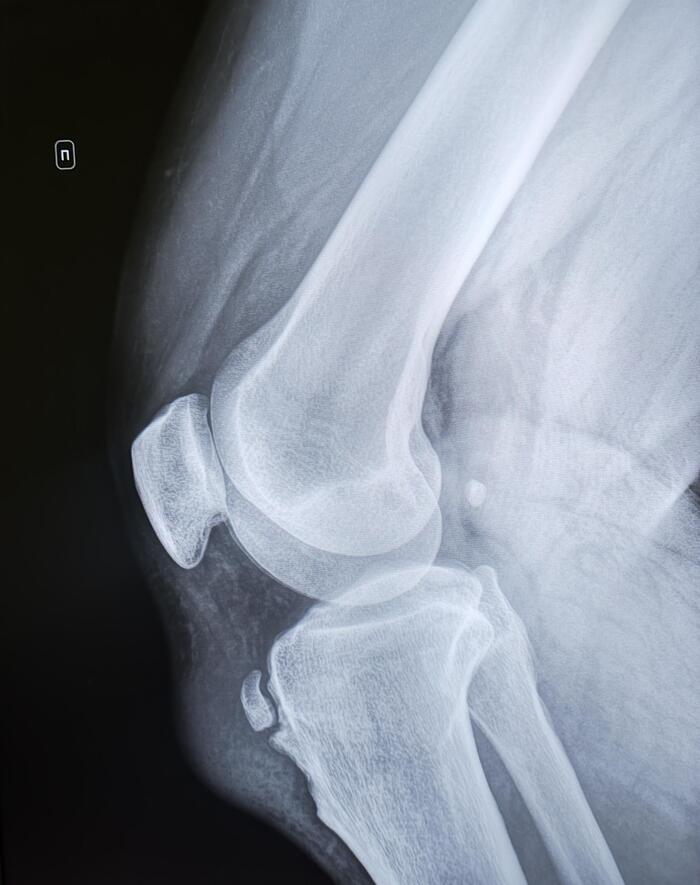

Призывник упал на вытянутую левую руку, обратился за помощью в травмпункт, где был диагностирован закрытый перелом дистального конца диафиза левой локтевой кости со смещением, выполнена закрытая репозиция, наложена гипсовая лонгета, на рентгенологический контроль призывник явился через 2 недели с момента перелома.

При повторном рентгенологическом исследовании выявлено вторичное смещение костного отломка латерально, нарушение оси левой локтевой кости, ее искривление в 17.4 град. Формирующаяся костная мозоль- что по сути означает срастания перелома. Заключение: Неправильно срастающийся перелом дистального конца левой локтевой кости со смещением.